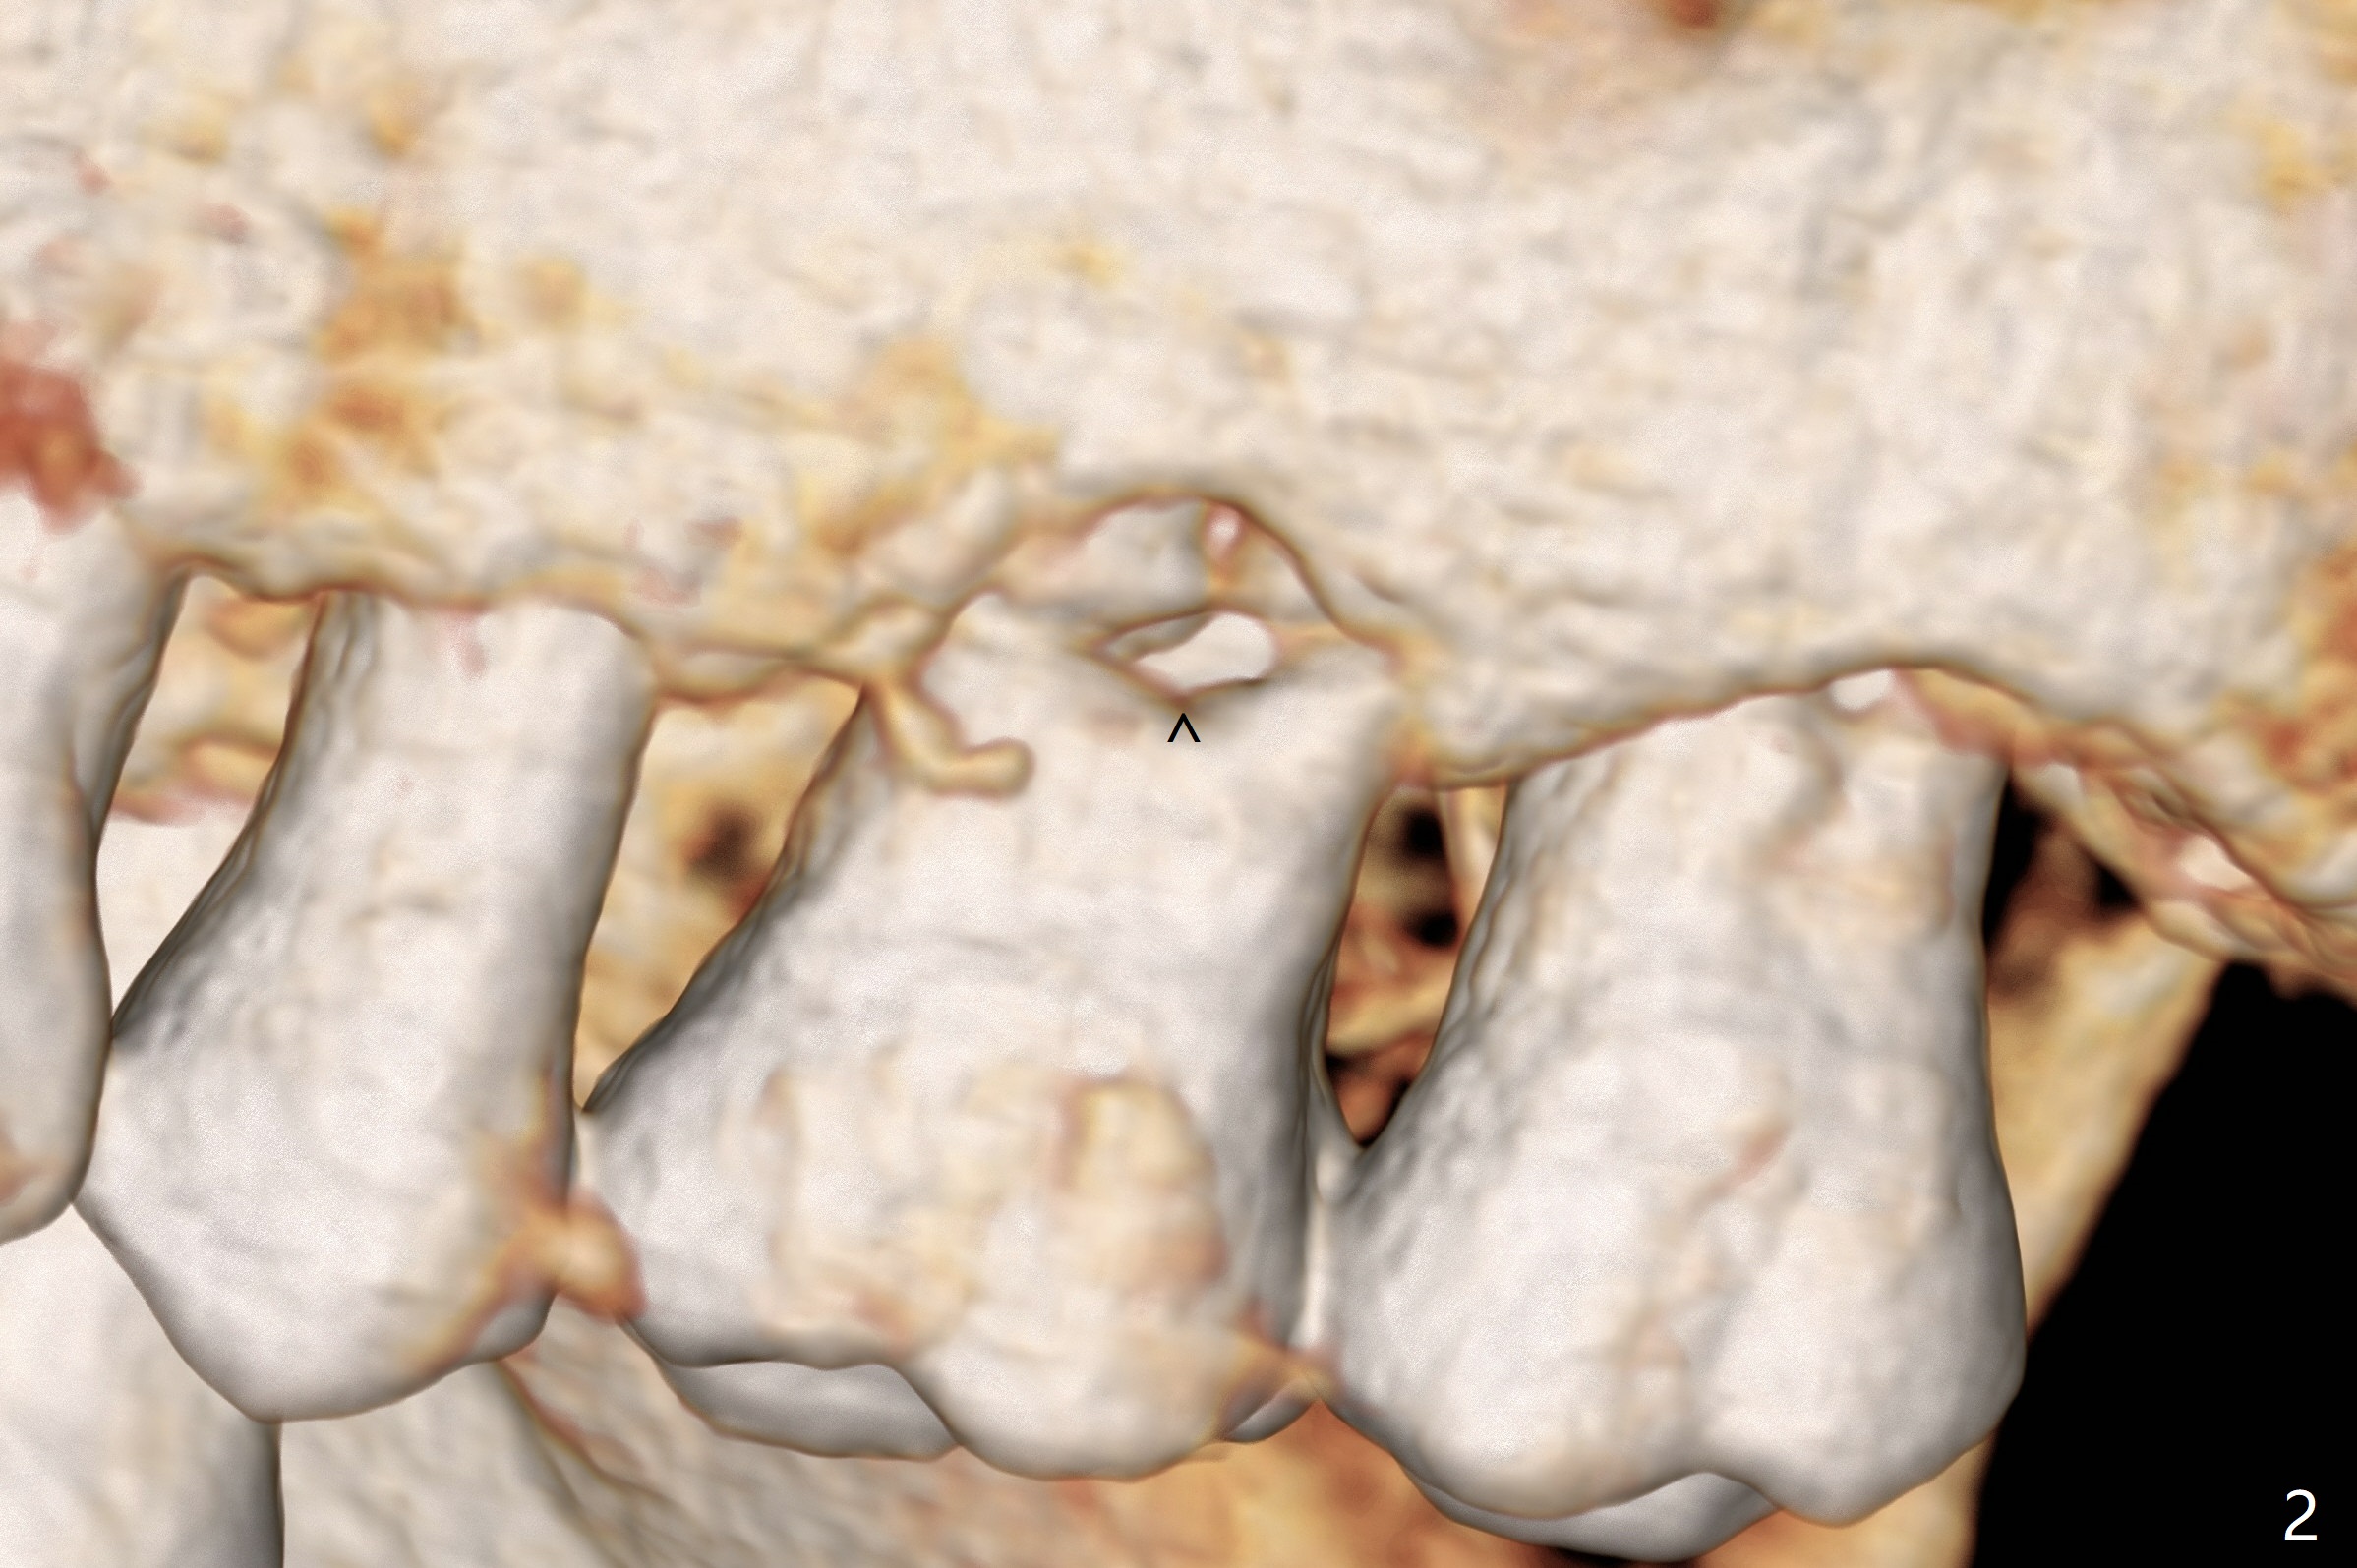

A 60-year-old man had buccal furca abscess at #14 with an unknown radiolucent lesion within the tooth five months earlier (Fig.1 *). Now the tooth is sensitive to cold. CBCT shows internal resorption involving the mesiobuccal and distobuccal roots (Fig.3,4 (axial section) *) with exits mesially (Fig.3 >) and buccally (Fig.2 ^). There is periapical radiolucency of MB (Fig.3,7) with the thickened overlying sinus membrane (Fig.3,5,6 (*), as compared to that over the tooth #3 (Fig.6)). Osteotomy will be established in the septum away from the lesion (Fig.8 red circle) and for 5 mm (Fig.5 (coronal section)). He is a heavy bruxer, loosening Ketac-cemented unipost. Use PRF to repair the defect associated with the MB lesion and sinus lift.